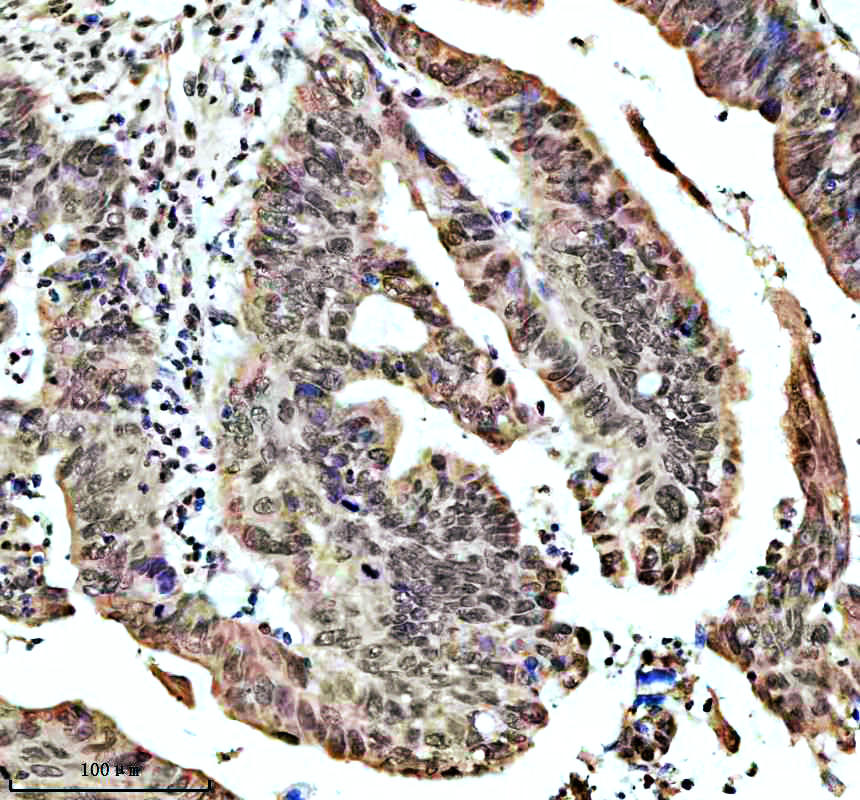

IHC analysis of SHP2/PTPN11 using anti-SHP2/PTPN11 antibody (BM4588) .

SHP2/PTPN11 was detected in a paraffin-embedded section of human colon cnacer tissue. The tissue section was incubated with rabbit anti-SHP2/PTPN11 Antibody (BM4588) at a dilution of 1:200 and developed using HRP Conjugated Rabbit IgG Super Vision Assay Kit (Catalog # SV0002) with DAB (Catalog # AR1027) as the chromogen.